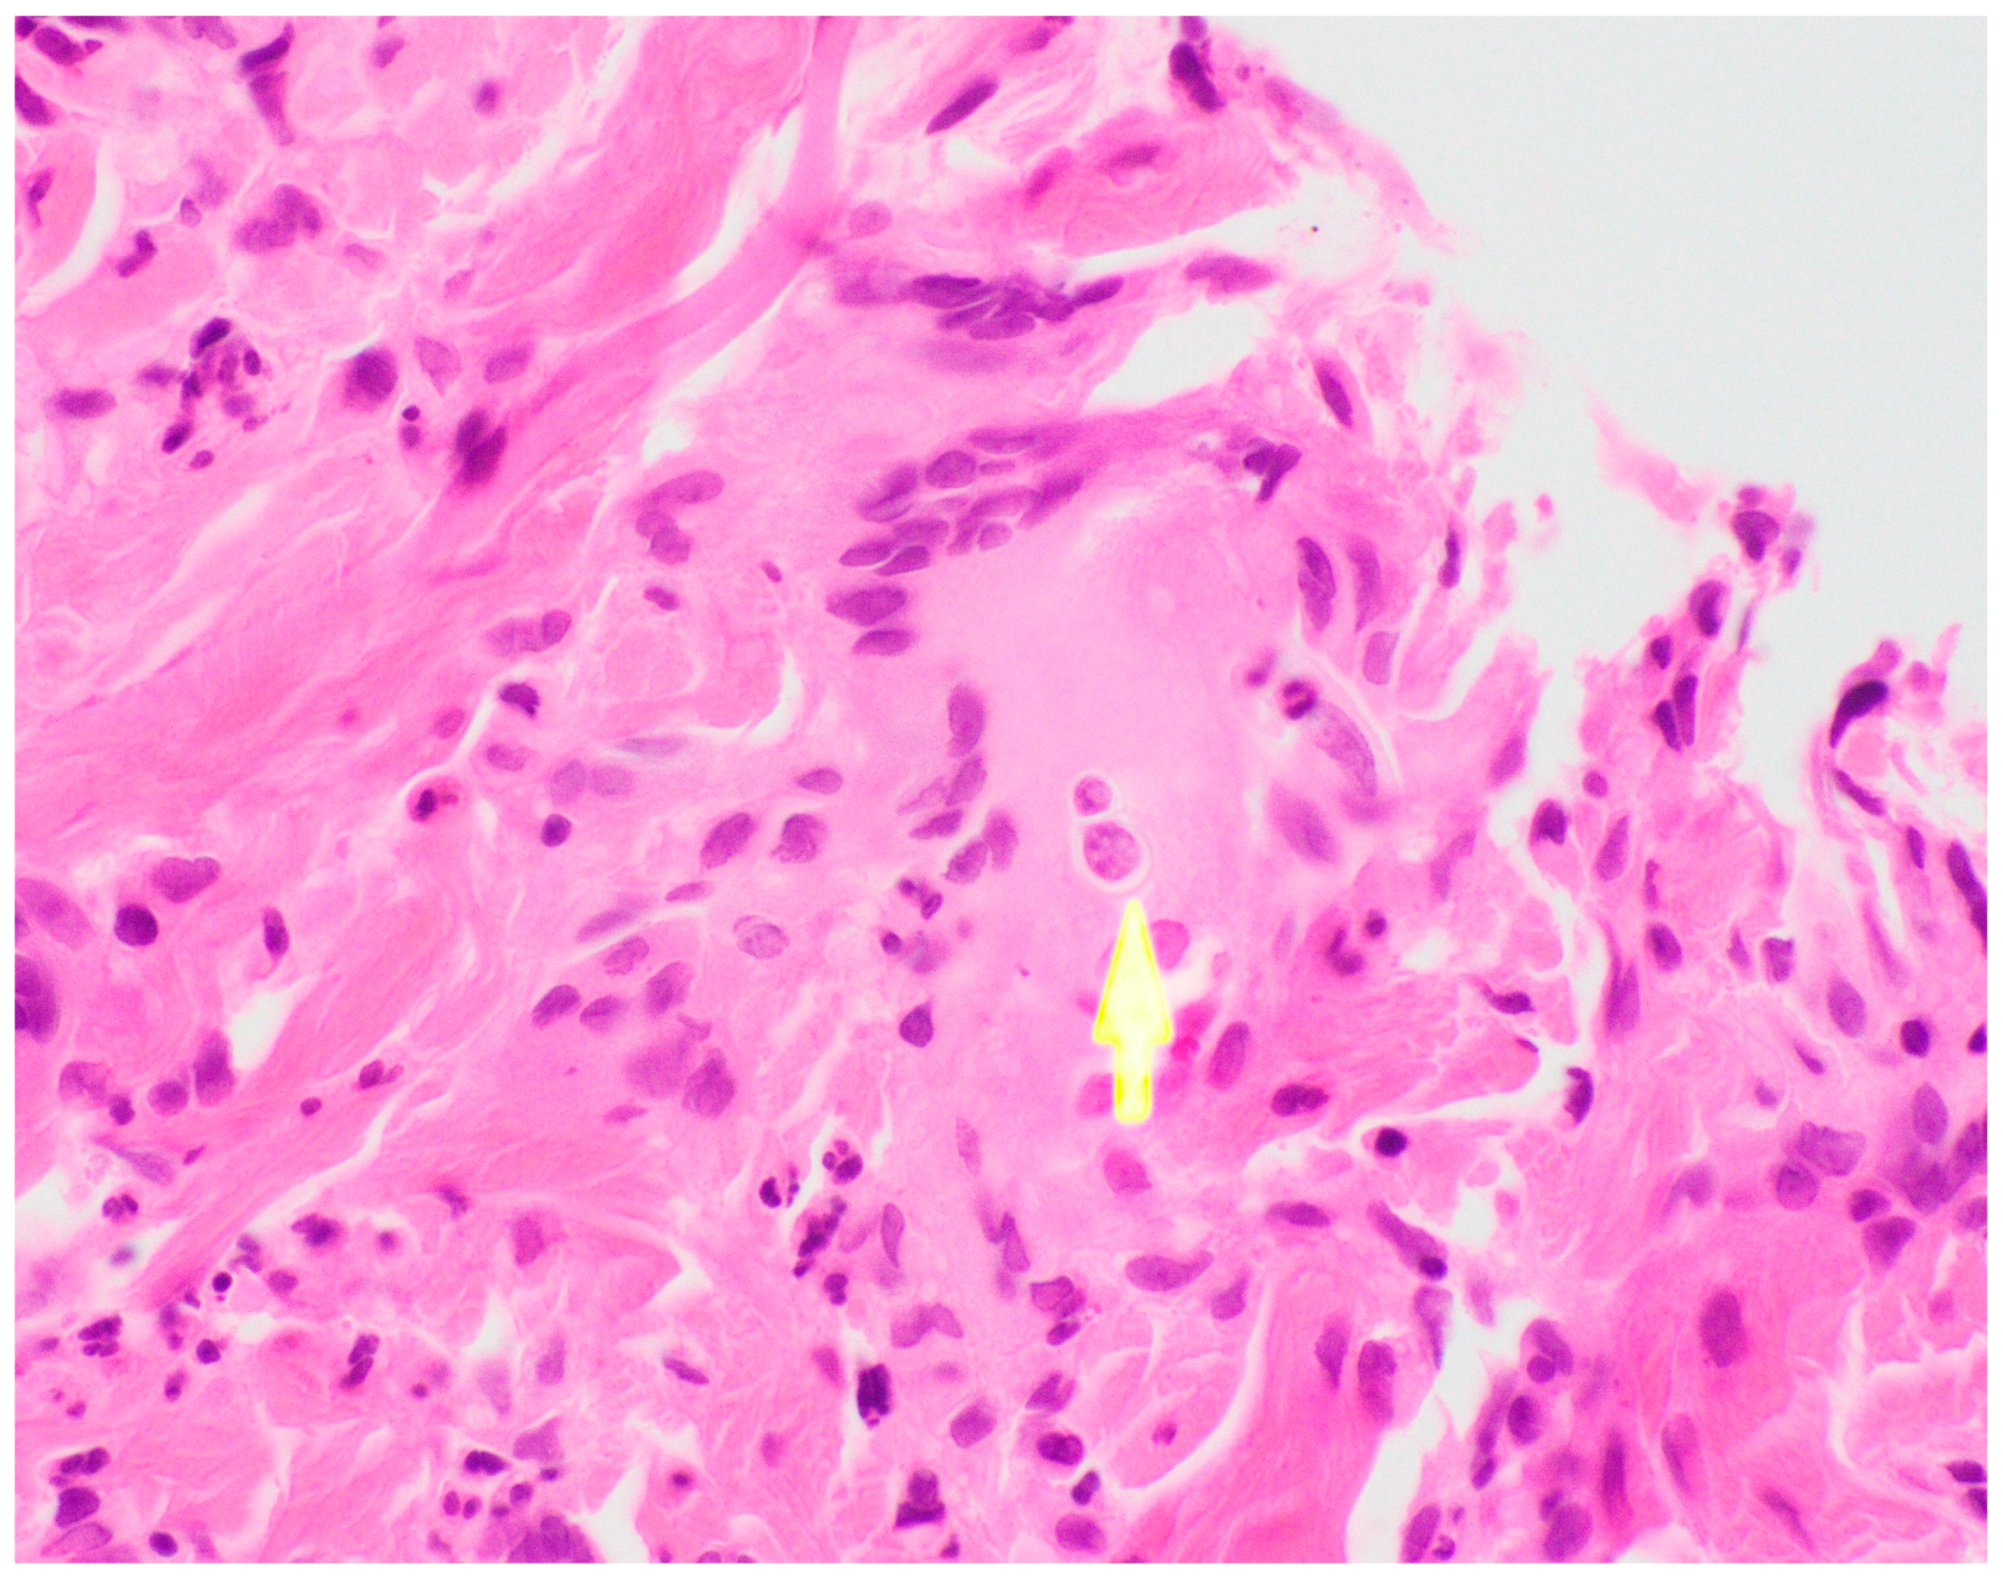

Ultimately, a punch biopsy of his left second metacarpophalangeal joint was taken in addition to cultures from the left hip sinus tract drainage which revealed the presence and growth of Blastomyces dermatitidis after 12 days of hospitalization, respectively (Figure 4 and Figure 5). Serology testing was also ordered, which was positive for Blastomyces antibody immunodiffusion (ID), though negative for Blastomyces antibody complement fixation (CF). Notably, a urine histoplasma antigen test was positive with a result of >25.0 ng/mL with a negative histoplasma antibody ID test, likely indicating a component of cross-reactivity in the presence of Blastomyces dermatitidis.

Figure 5. Left 2nd MCP biopsy, H&E stain demonstrating characteristic broad-based budding seen in Blastomyces infections.